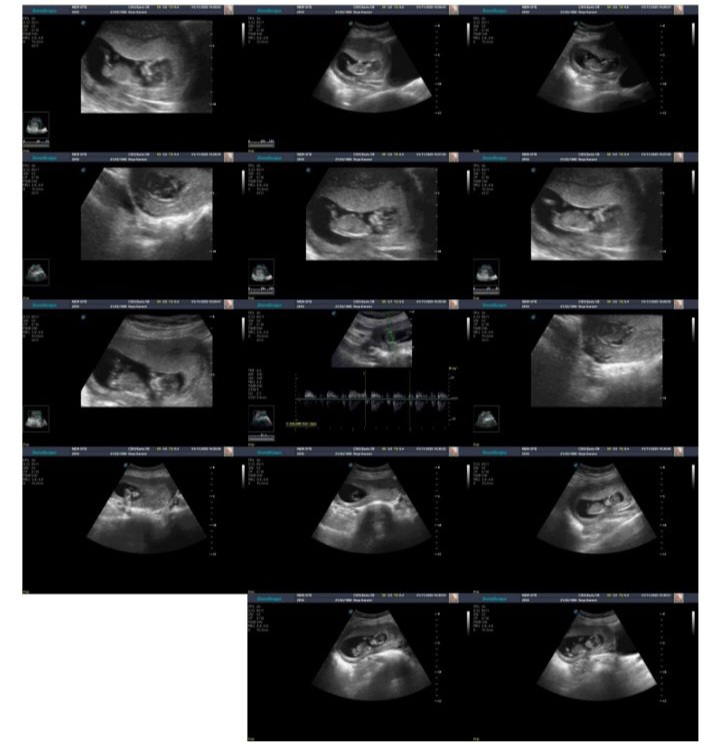

zendegemeeshgam مدیر استارتر عضویت: 1397/01/04 تعداد پست: 2204 عنوان لطفا بیایید 21 بازدید | 1 پست تعیین جنسیت 😊دخترم توامید🤩وزیبایی 🤩رو ب زندگیم بخشیدی😌😌 1404/08/10 | 15:11 0 نفر لایک کرده اند ... گزارش تاپیک نامناسب

zendegemeeshgam مدیر استارتر عضویت: 1397/01/04 تعداد پست: 2204 😊دخترم توامید🤩وزیبایی 🤩رو ب زندگیم بخشیدی😌😌